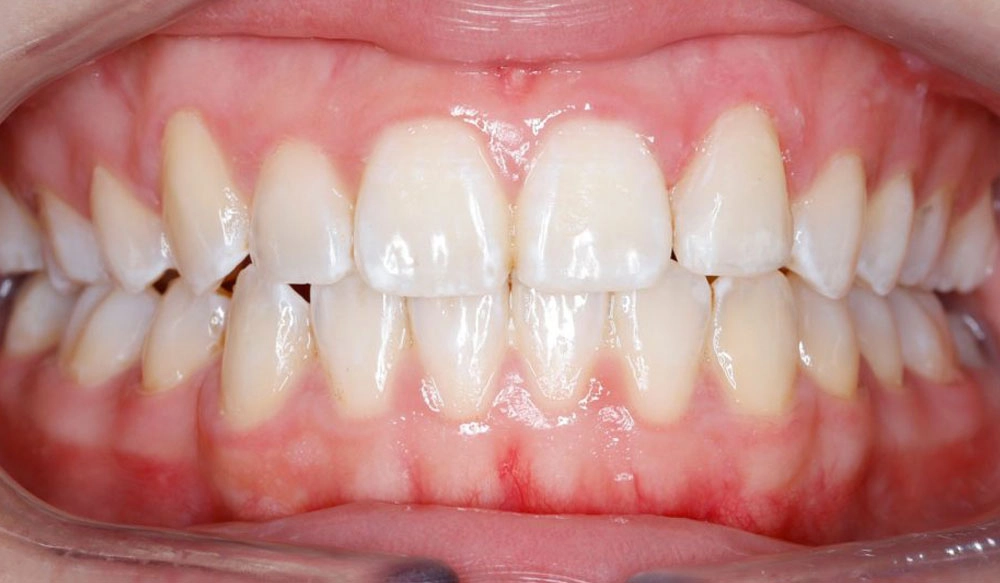

Narrow Arches

Narrow arches is the condition in which the transverse width of the maxillary and/or mandibular arches is too narrow for the teeth to properly align and have good occlusal contact.

Patient Information:

Age: 21

Gender: Female

Invisalign Treatment Option: Invisalign Comprehensive

Total Treatment Time:

11 months